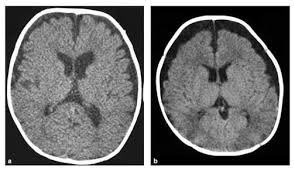

1️⃣مع تقدمك في العمر تفقد طبيعياً بعض خلايا المخ بشكلٍ بطيء،لكن قد يحدث فقدان سريع لتلك الخلايا بسبب اصابةالشخص بضمور المخ،فما هو هذا المرض،وماهي الأمراض المرتبطة به؟

ضمور المخ هو فقدان خلايا الدماغ التي تسمى العصبونات،فيؤدي إلى حدوث خلل في الاتصالات التي تساعد الخلايا على التواصل